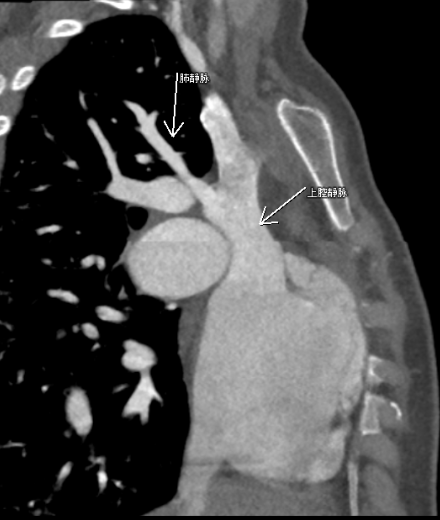

通过左房肺静脉CTA检查

张琳发现

阿珍的肺动脉高压

是先心病引起的

房间隔缺损导致

肺静脉异位引流

就是本该回到左心房的肺静脉血液

一部分汇入到了上腔静脉